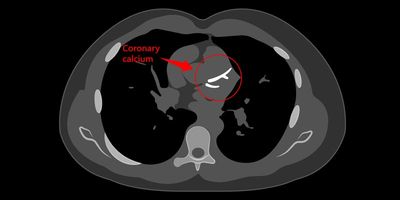

CAC Score (Coronary Artery Calcium Score), adalah pengukuran jumlah kalsium yang menumpuk pada pembuluh darah jantung (arteri koroner). Penumpukan kalsium ini merupakan tanda adanya plak aterosklerosis, yaitu kondisi di mana lemak, kolesterol, dan zat lain menempel di dinding arteri dan mengurangi aliran darah ke jantung.

Tes ini dilakukan menggunakan CT Scan tanpa kontras, sehingga tidak memerlukan suntikan atau prosedur invasif. Hasilnya berupa angka yang menunjukkan tingkat kalsifikasi, yang selanjutnya akan diinterpretasi oleh dokter sebagai indikator risiko penyakit jantung koroner.

Hasil CAC Score dinyatakan dalam skala numerik. Berikut interpretasinya: